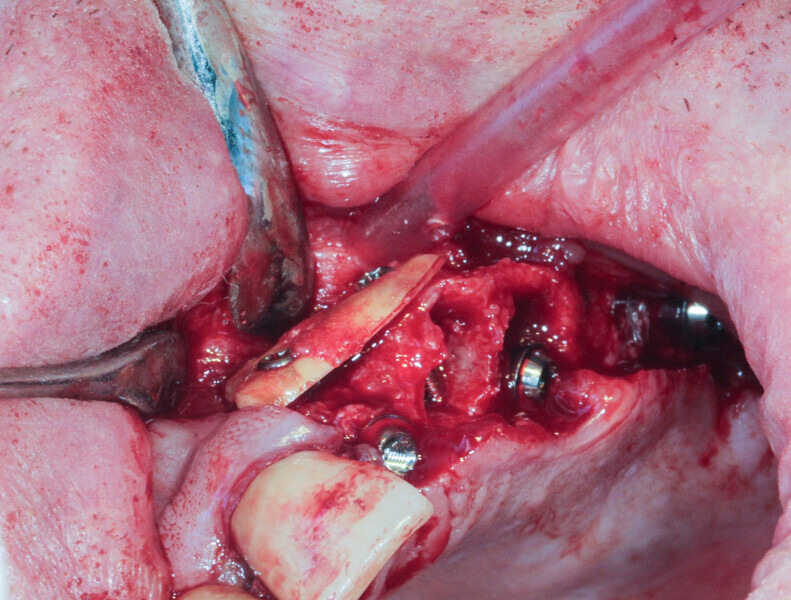

Case 2

A 62-year-old patient with a bridge from tooth #21 to tooth #27 requiring replacement, teeth #21, 23, 24 and 27 with abutments and the crown of #22, 25 and 26 missing, was treated. The ridge of tooth #22 exhibited a transverse bone insufficiency which would have allowed the placement of an implant, but the aesthetic outcome would have been unsatisfactory (Fig. 10). First, the bridge of tooth #24 was sectioned distally and the root of tooth #27 extracted. After a two-month healing period, the patient was treated with simultaneous extraction, implantation and aesthetic restoration. The bridge was sectioned distally at tooth #21, a full thickness flap was elevated and the teeth #23 and 24 were extracted, allowing the bone defect at tooth #22 to be assessed (Fig. 11). Implants were placed into sites #22, 24 and 27. The root of tooth #23 allowed us to compensate for the bone defect and achieve a satisfactory aesthetic result. The root was prepared as described. The radicular graft was fixated away from the ridge, the edges of the graft in contact with the alveolar bone (Fig. 12). The spaces between the ridge, the graft and the alveoli were filled with a synthetic, hydroxyapatite-based biomaterial, the flap was stretched and sutured around the healing abutments, an impression was taken, and a temporary prosthesis from implant #22 to 27 was made during the day by the laboratory and fitted the same evening. The stitches were removed on the tenth day and the bridge after two months to check for the successful osseointegration of the implants. The osteosynthesis screws were not removed in this case because they were not visible under the gingiva (Figs. 13 & 14). A CBCT assessment was performed after six months to check that the graft had taken successfully. Finally, our colleague fitted the definitive prosthesis.